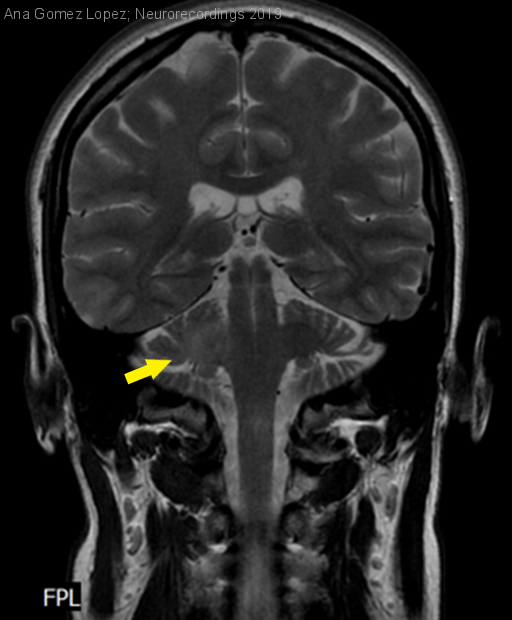

Mujer | 33 años

Diagnóstico final: Encefalitis de tronco asociada a anticuerpos anti-MOG

Resumen del caso

Mujer de 33 años, con antecedente de meningitis linfocitaria aséptica en 2010, y de episodio de diplopía de una semana de duración en 2016 por el cual fue estudiada en otro centro con EMG y...